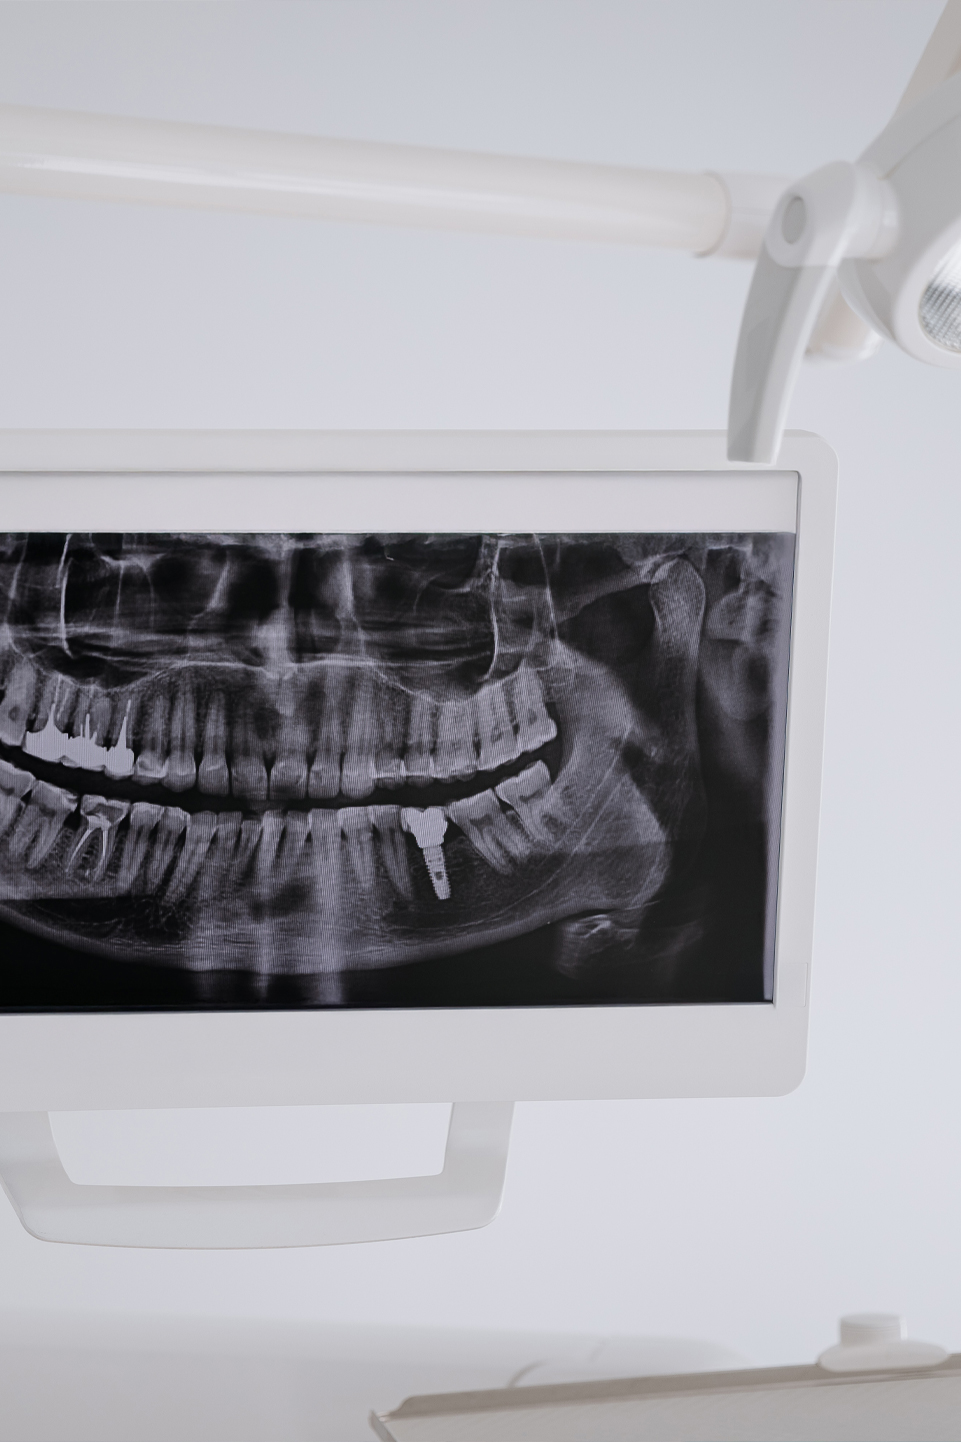

Au sport ou au terrain de jeux il arrive de recevoir un choc sur une dent « avant ». Bien que non brisée celle-ci peut être sensible quelques jours, la gencive peut saigner légèrement. Le mieux est de consulter votre dentiste dans les jours qui suivent le choc afin de vérifier la vitalité pulpaire de la dent et vérifier l’intégrité de la racine et de l’os entourant la dent.

Si la dent n’est pas sensible vous pouvez attendre votre rendez-vous de nettoyage et mentionnez le à cette occasion. Des blessures invisibles à l’œil et sans symptômes immédiats peuvent se produire. Une fracture de la racine ou une fêlure de la dent pour un œil inexpérimenté seront imperceptibles.

Vous avez reçu un coup à la bouche ou fais une chute dont un impact s’est ressenti au niveau des dents, mais aucune dent ne semble d’apparence brisée, aucune douleur jusqu’à quelques jours par la suite ne surgit. Il serait préférable de le mentionner lors de votre prochain contrôle à la clinique afin de faire un examen approfondi de la zone. Des blessures invisibles à l’œil et sans symptômes immédiats peuvent se produire. Une fracture de la racine ou une fêlure de la dent pour un œil inexpérimenté seront imperceptibles.